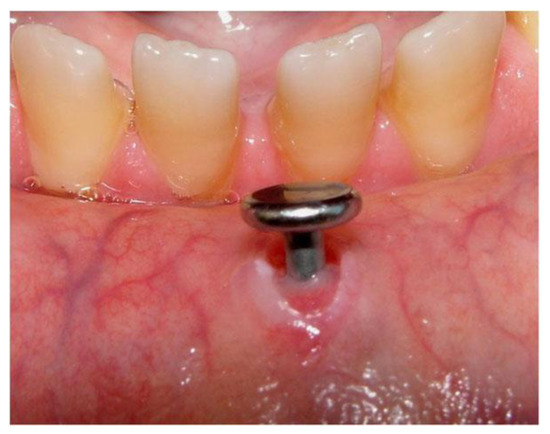

Figure 5.

Enamel fracture of the maxillary left central incisor due to tongue piercing [4].